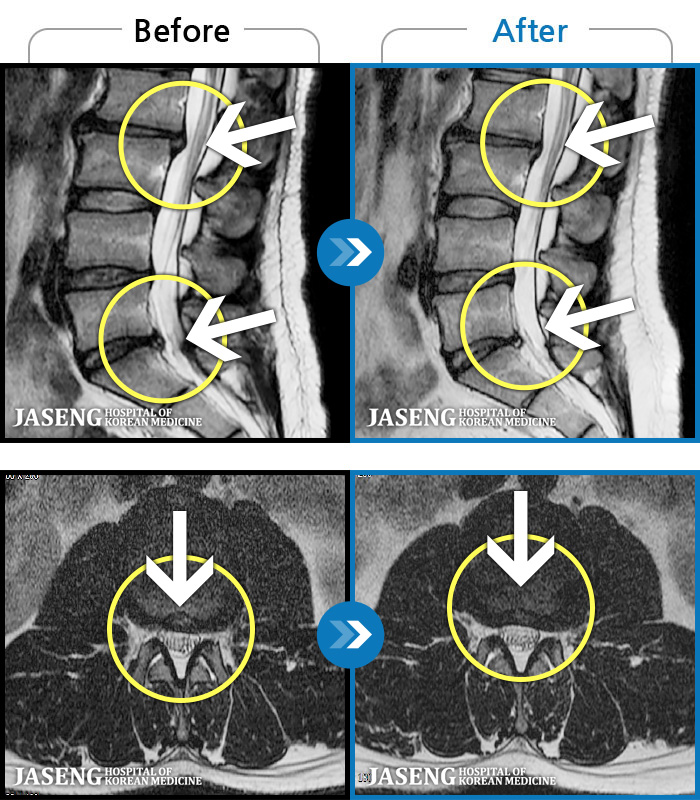

56 MRI ũ ʸ Ȯϼ.

Ƹ ϰ ־.

[õ] 25.03.18~25.07.22

[õ_㸮ũ] Ƹ ϰ ־.